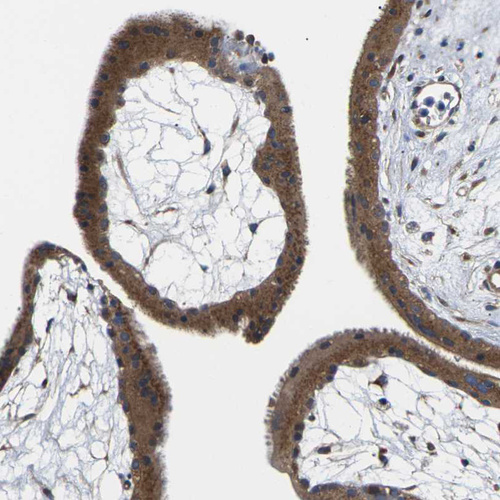

Immunohistochemistry analysis in human bone marrow and liver tissues using HPA014254 antibody. Corresponding TMCC2 RNA-seq data are presented for the same tissues.